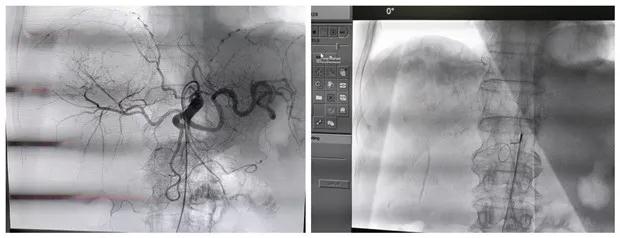

患者男性,69岁,因“右胁部胀痛伴乏力3月,发现肝占位2天”。入院行MRI检查提示:右肾癌并出血,肝内及腹膜后淋巴结多发转移。与彩超室韩娟娟主治医师配合行彩超引导下肝脏肿瘤穿刺术,取病理示:查见低分化腺癌,倾向于透明细胞型。

明确诊断后,经科室讨论考虑,患者为肿瘤晚期,失去外科手术机会,经肝动脉及肾动脉栓塞化疗是目前治疗不能手术切除肿瘤的最好治疗方法。经与患方充分沟通后,给予行肝动脉及右肾动脉栓塞化疗术,手术顺利,术后患者恢复良好。